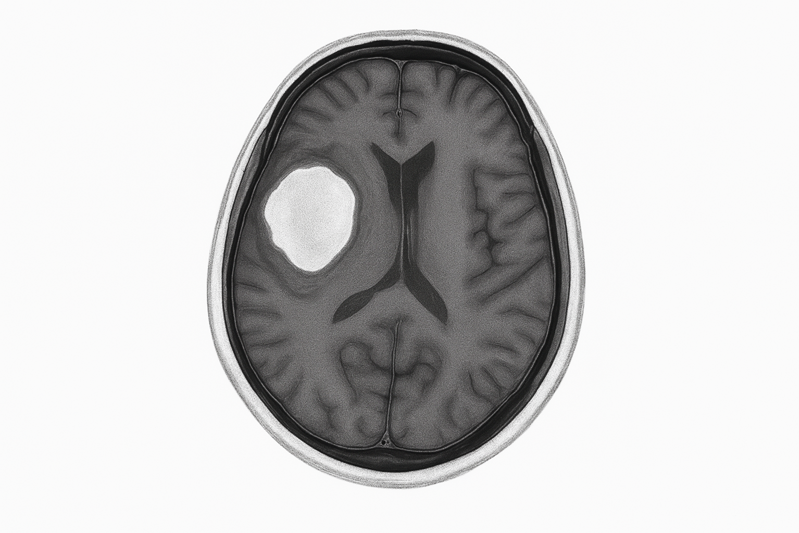

2013年,季女士突然莫名其妙地晕倒。经过脑部MRI(磁共振)检查,她的大脑深部、名为左岛叶的区域竟然发现了一个约6公分的肿瘤。医生初步判断,很可能是低级别胶质瘤。

约翰逊教授向她详细说明了现状:“经过我与肿瘤内科、放射科、外科等多学科团队共同讨论,我们认为,以你目前的情况,手术只能切除约15%-20%的肿瘤。根据你的MRI影像,有一小部分肿瘤位于前颅部,靠近额头,这里脑组织相对较少,可以较干净地切除。但剩余的大部分肿瘤与大脑左侧及后部的重要组织和神经紧密相连,无法在不造成严重损伤的情况下强行切除。”